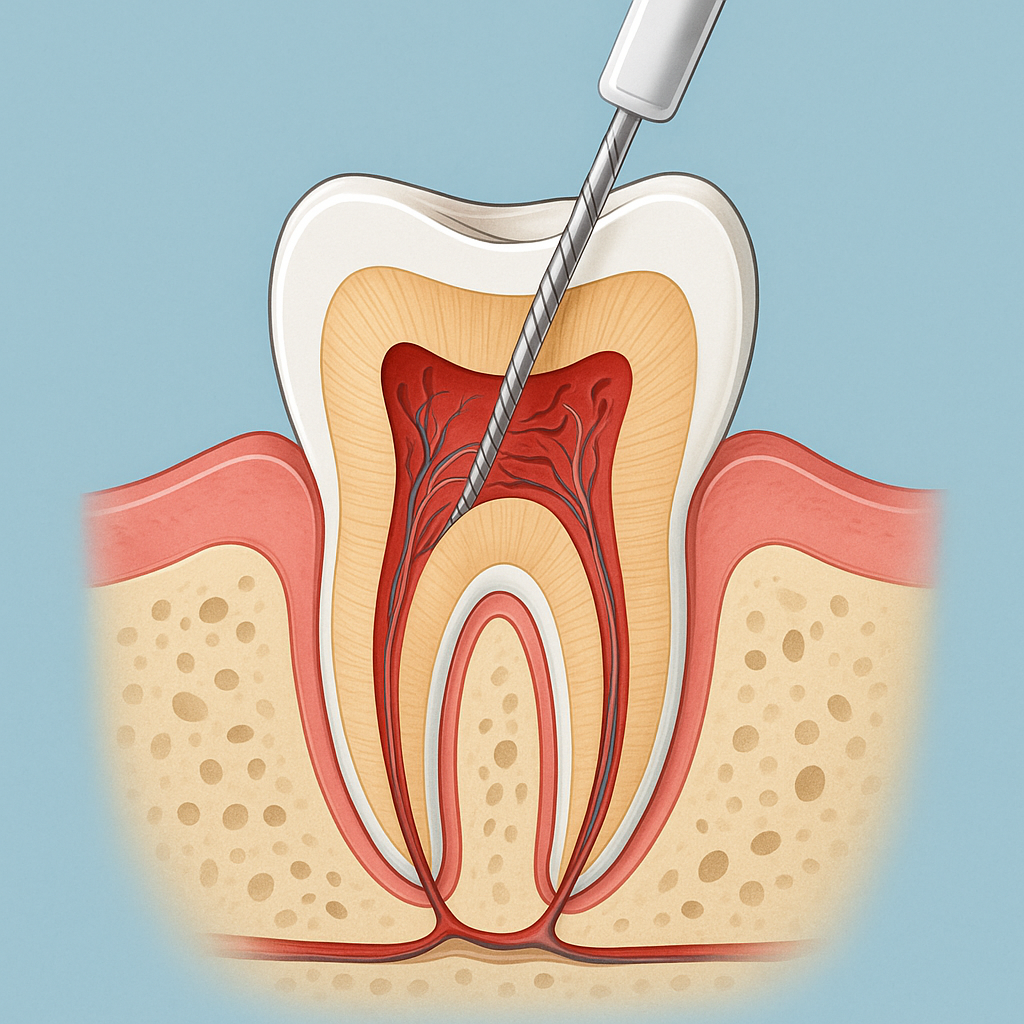

JP Dental Clinic is a leading dental clinic in Koramangala, Bangalore, providing comprehensive dental care with a focus on comfort, precision, and long-term oral health. Our experienced dentists offer advanced treatments including dental implants, root canal treatment, braces and aligners, veneers, teeth whitening, and pediatric dentistry.

Dr. Jaipal Reddy is an experienced and highly regarded dental surgeon and cosmetic dentist based in Koramangala, Bengaluru. He is the founder and lead dentist at JP Dental Clinic, a well-established dental practice known for comprehensive, patient-centric oral care. Dr. Reddy holds a Bachelor of Dental Surgery (BDS) degree from the Government Dental College and Research Institute, Bangalore, and brings over 25 years of clinical experience in general dentistry, endodontics, and cosmetic dental procedures.